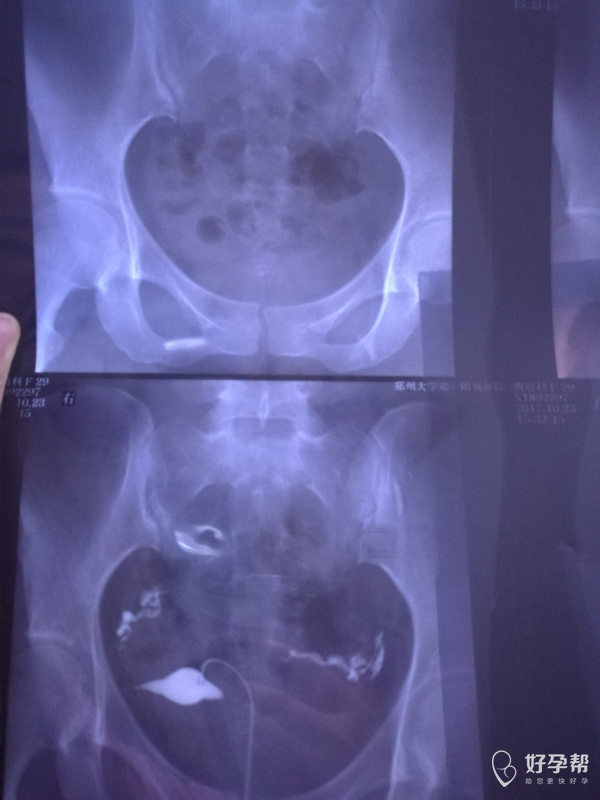

医生帮我看下造影片子???

您好,双侧输卵管通畅的,可以怀孕试试

天边回复赵敏英:右侧是不是有点粘连,上举

考虑盆腔有点粘连可以考虑行腹腔镜手术,建议结合您年龄等综合考虑,祝您好孕,欢迎咨询,满意请点击采纳

天边回复罗棹文:严重吗?影响怀孕不

完善男方精液检查,若结果正常建议监测排卵指导同房三月未孕则可考虑行腹腔镜手术

看着还可以,可以先试孕